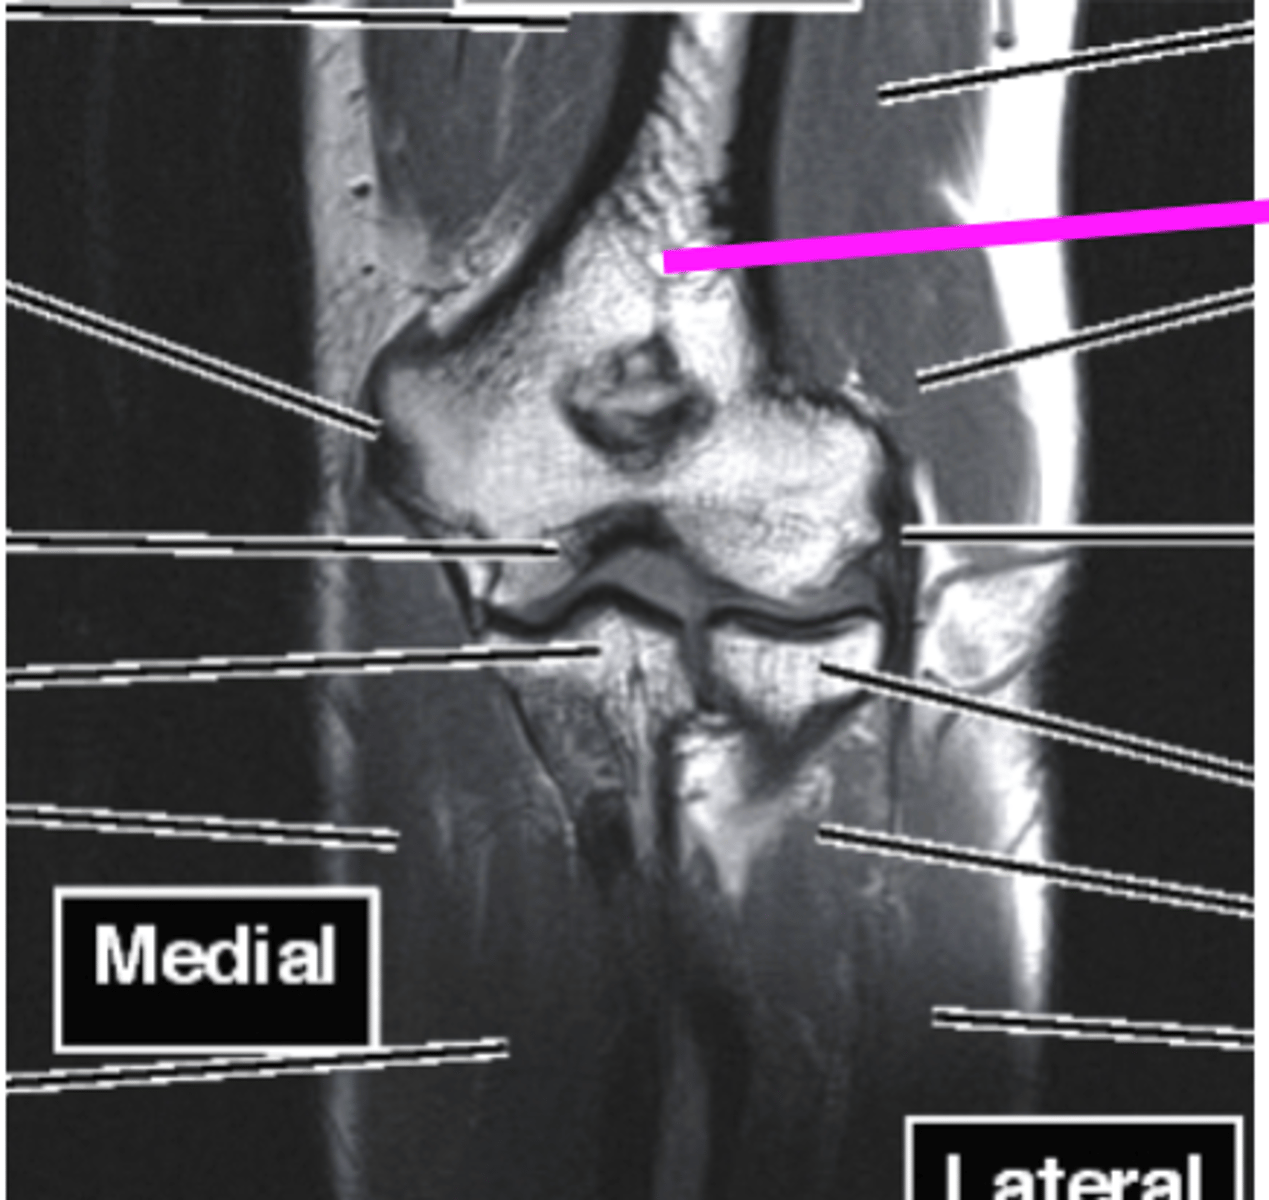

Elbow MRI

what type of imaging is this?

humerus

what does this pink line point to?

ulna